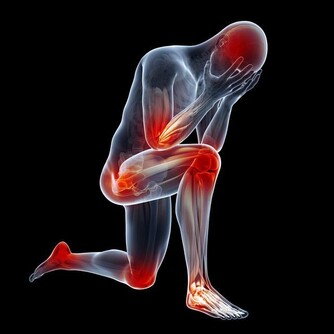

5、 乳酸

這五種毒素是女性衰老催化劑,必須盡快排出

人體什麼時候會產生乳酸呢?當我們經常處於疲勞狀態的時候就很容易出現腰酸背痛、渾身乏力、反應遲鈍等等這些症狀。其實這些都是由於乳酸堆積過多而造成的,乳酸是人體長時間運動過程中產生的,它會和焦化葡萄糖酸在體內不斷地累積,從而就會導致血液呈酸性。文章來源: https://wj.toutiao.com/q/125515/9R9jL421/6d22/#/